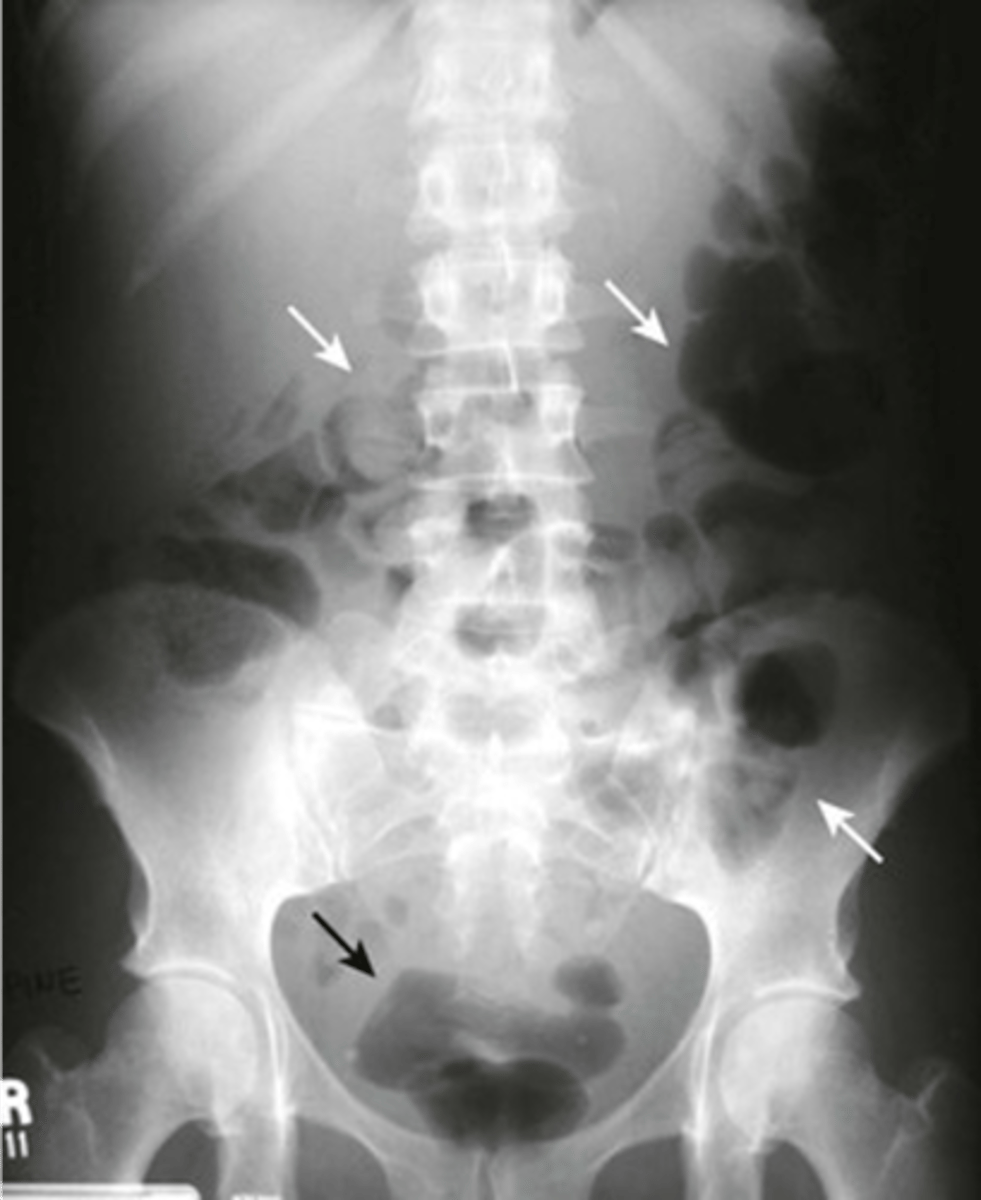

Abnormal organs on AXR

Hepatomegaly

Hepatomegaly (pic 2)

splenomegaly